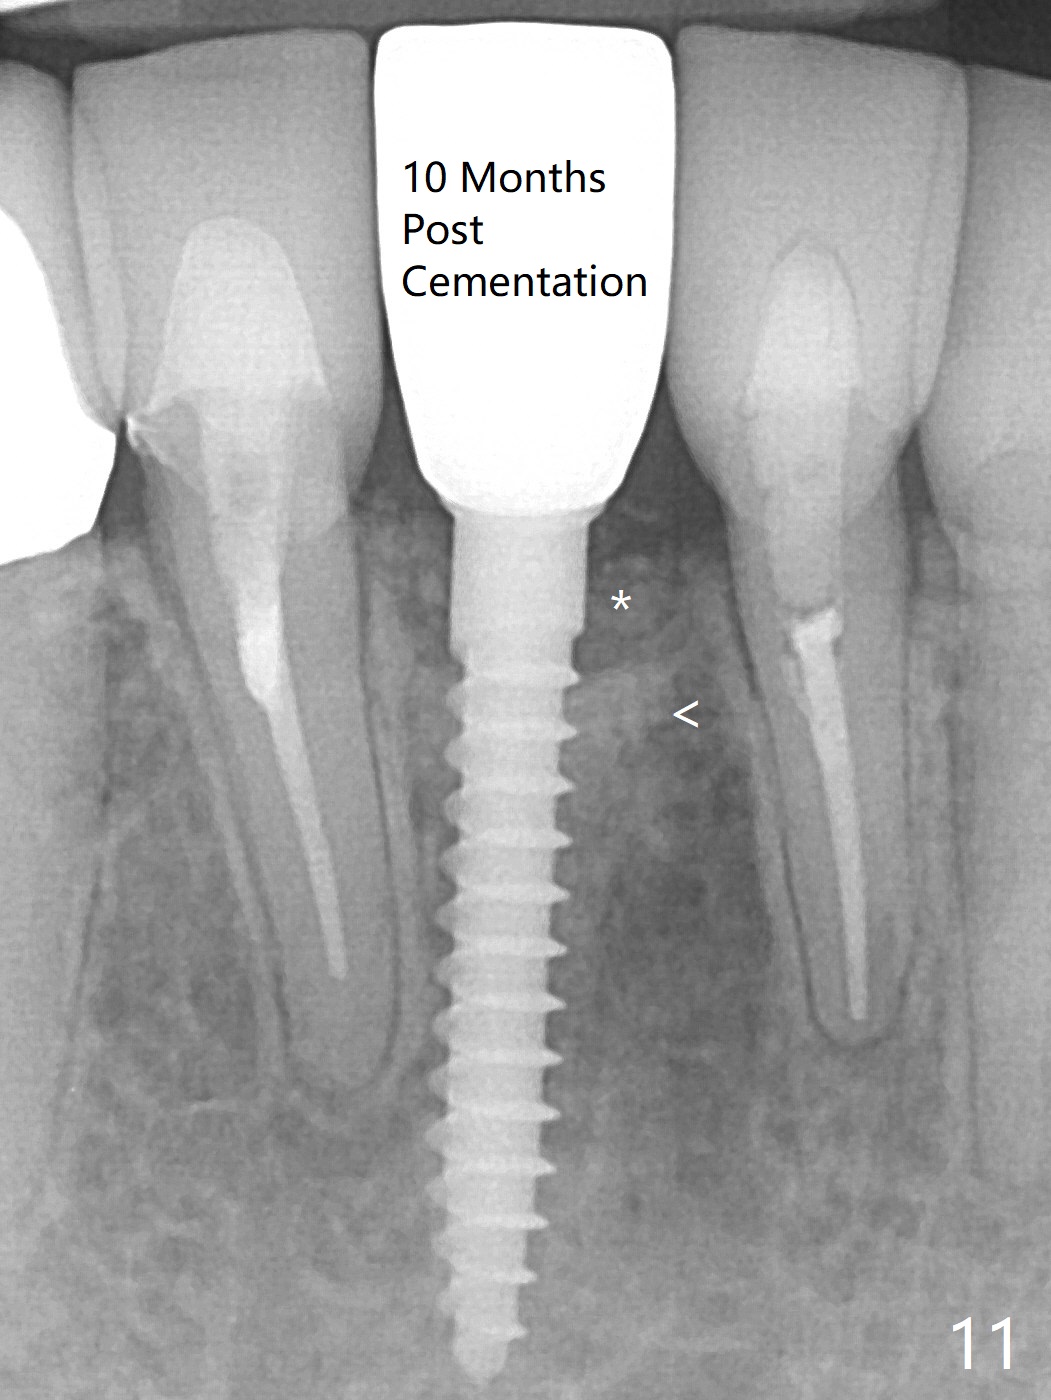

A drawback of implant planning at #25 is not to use a preop PA (Fig.1 (^ fracture line)). The initial trajectory seems to be alright (Fig.2), but a 2.5x14(2) mm implant placed is close to the tooth #26 (Fig.3). In fact the affected tooth is deviated distal; osteotomy should be initiated in the mesial slope of the socket (Fig.4 red line). The final trajectory appears to be perfect (Fig.5). Furthermore the 1st intraop PA should be analyzed carefully (Fig.6). A new osteotomy should be established mesial or the existing one should be moved mesial with Lindamann bur (Fig.7). The distal implant placement may be related to more bone loss in the distal crest 3.5 months postop (Fig.8) and more severe distal papillary recession (Fig.9 *). The bone density increases at the levels of the non-thread and thread portions of the implant (in the original socket) nearly 10 months post cementation (Fig.11 *, <). There is no bone loss 16 months post cementation (Fig.12).